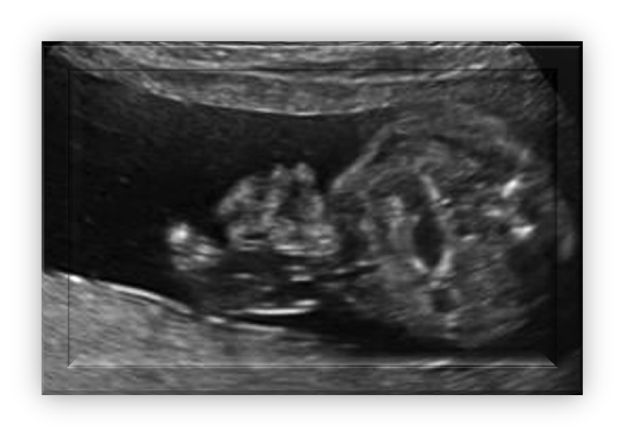

bowel obstruction

Bowel dilation